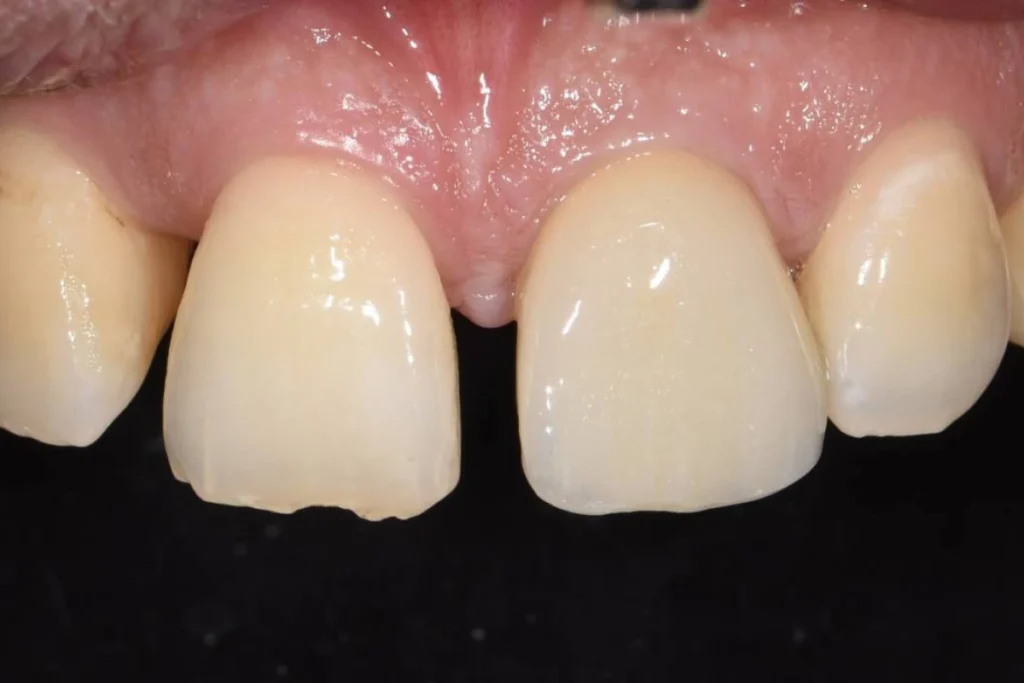

L’intervention est réalisée sous anesthésie locale et doit être complètement indolore. Le patient est revu 3 mois après l’intervention pour prendre une empreinte. Le patient est invité à se rendre au laboratoire de prothèse situé dans le 17ème afin de discuter de la forme de la dent avec l’artisan céramiste. Dans le cas présent, il souhaitait conserver l’écart existant entre ces incisives afin de conserver l’identité de son sourire.

Lors de cet entretien, le prothésiste enregistre également toutes les données de teinte et d’état de surface des dents adjacentes afin de faire la parfaite illusion d’une dent naturelle.

Environ une semaine après la prise de l’empreinte, un essayage est réalisé au cabinet. Si tous les paramètres esthétiques et fonctionnels sont validés, la couronne est posée dans la foulée.

Il est parfois nécessaire de prendre le temps d’une retouche au laboratoire afin d’obtenir le rendu escompté.